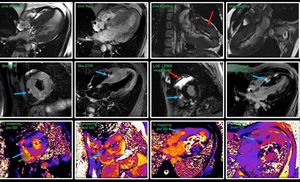

MRI conditional pacemaker / cardiac imaging. Siemens AERA, 1.5 Tesla. Even though these pacemakers can be scanned, it doesn’t mean we get images without artifacts. Should we say no to all these patients due to artifacts and suboptimal images? Answer should be no. Patient with a cardiac tumor where we utilize standard sequences like cine truefisp (looks awful due to artifacts, red arrow). STIR, T1 mapping pre Gd along with T1 mapping post Gd and LGE gave us the answer to the question for this patient (blue arrow). It’s not always about the perfect images, but about answering the clinical questions. Images courtesy of Bac Nguyen.